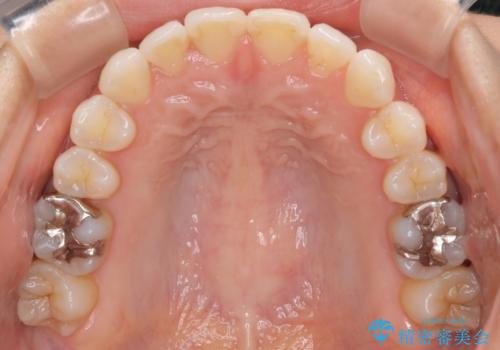

八重歯と前歯のガタガタをインビザラインで

- 八重歯と前歯のガタガタを主訴に来院されました。

目立たず矯正したいとのことでインビザラインで矯正することとしました。

インビザラインで目立たずに治療を終えることができ、喜んでいただけました。